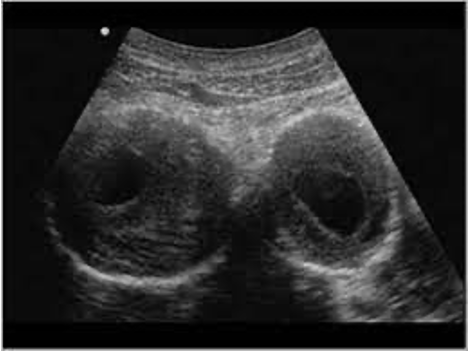

This patient most likely has which of the following pathologies?

may-thurner syndrome